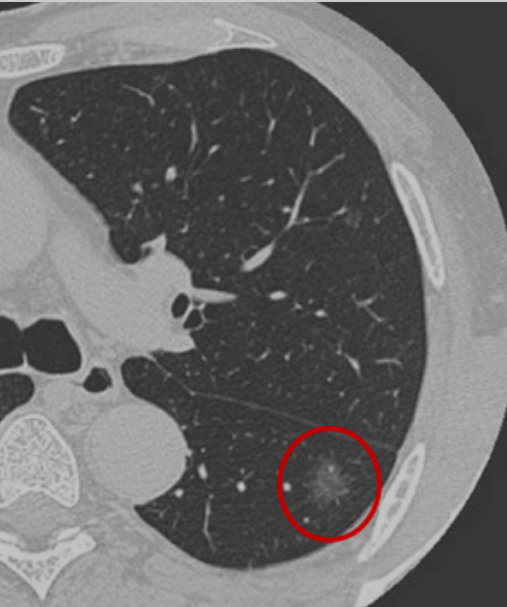

肺结节是指在肺实质内而不属于正常肺组织的结节状阴影,在肺部影像表现为直径小于30厘米的类圆形、密度增高、局灶性的实性或者亚实性肺部阴影,可为孤立性或多发性,不伴肺不张、肺门淋巴结肿大和胸腔积液。80%以上的肺结节都是良性的,如肺结核、肺良性肿瘤、肺炎、肺动静脉畸形等,当然也有部分结节是恶性的,而小部分肺良性结节在随访的过程中可能出现恶变。

根据胸部CT判断是否存在磨玻璃密度成分,可将肺结节分为:纯磨玻璃结节、实性结节和部分实性结节。磨玻璃结节又叫磨玻璃影、毛玻璃结节等,表现为密度轻度增高的云雾状淡薄影或结节,在CT上跟磨砂玻璃一样。按病理性质,磨玻璃结节可以是良性病变如炎症或出血、局灶纤维化等,或者是癌前病变如原位腺癌、非典型腺瘤,也可以是恶性肿瘤如转移癌、微浸润腺癌等。

肺癌高危结节是指可能成为肺癌或转变为肺癌风险较高的肺结节,主要表现为直径≥1.5厘米或直径介于0.8至1.5厘米之间但表现出毛刺、分叶、胸膜牵拉、含气细支气管征和偏心厚壁空洞、空泡征等恶性CT征象的结节,以及直径大于0.8厘米的部分实性结节。此外,还需结合患者是否有肺癌家族史、长期吸烟史或患有其他恶性肿瘤病史等危险因素。高危结节通常需要经验丰富的影像科、肿瘤科、呼吸科或胸外科等医生进行综合判断。